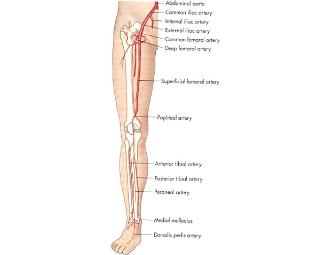

Lower Extremity Arterial Doppler Studies

Description: The Arterial Doppler ultrasound uses sound waves at a frequency that is higher than humans are able to hear to produce images on a monitor for the purpose of evaluating the arterial blood flow to the lower extremities (legs).

Indication: The Arterial Doppler study is able to demonstrate blocked or reduced blood flow through the major arteries of the legs. It is used to evaluate: